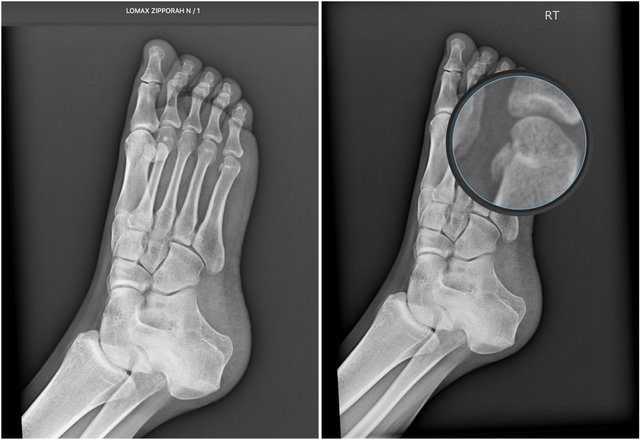

I finally met with a podiatrist on the 28th. As I strongly suspected, the radiologist who claimed my foot was 'normal' – that my x-rays revealed 'nothing of concern' – was either high or lazy.

Just as I was told the day it happened, there's a displaced fracture or 'chip' on the head of the 5th metatarsal on my right foot. As well, the doc suspects I have a non-displaced fracture on the head of the 4th. He could see that the heads of the 3rd, 4th and 5th were all smashed, the 4th appearing a bit 'torqued', as well.

The good news is – no surgery necessary. Though I can't presently move my little toes, the doc thinks I'll regain full mobility eventually.

So...I've got at least 4 more weeks in the boot. Then more x-rays, and we'll see if I can start thinking about driving again.